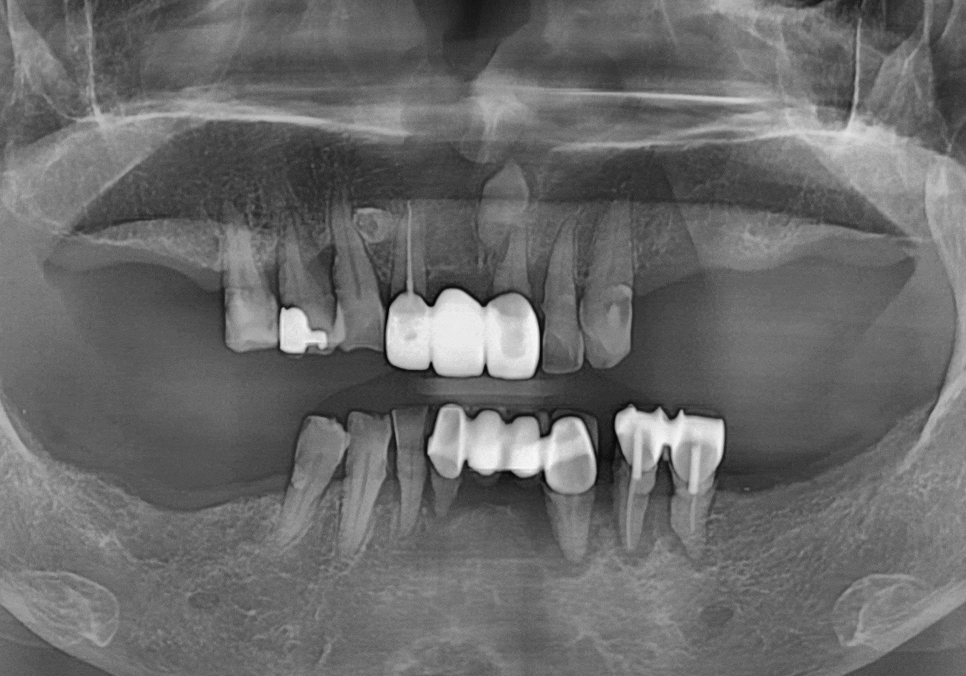

과거의 일반적인 임플란트 방식은

의료진의 경험과 2차원적인 엑스레이에

의존해 식립 위치를 결정하는 경우가 많았어요.

이 환자분 케이스에서 가장 중요했던 점은

아래턱을 지나는 하치조 신경을

완벽히 피하는 것인데요.

만약 임플란트가 이 신경을 조금이라도 건드리면

안면 마비나 감각 이상 같은

심각한 부작용이 생길 수 있기 때문에

주의해야 하는 구조물 중 하나입니다.

일반적인 방식이었다면

의사의 감각에 의존해 신경관과의 거리를

가늠하며 조심스럽게 심었겠지만...

저희는 디지털 시스템을 활용하여

3D 데이터를 통해 신경의 위치를 미리 파악하고,

잇몸뼈가 가장 튼튼한 곳을 골라

최적의 각도로 설계를 마쳤습니다.